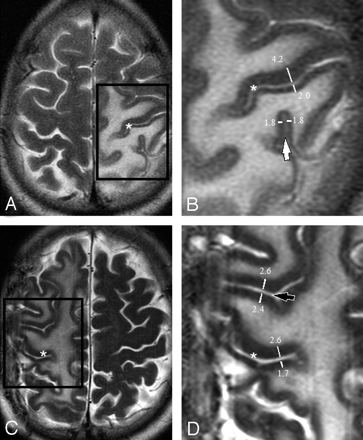

Differential cortical thickness across the central sulcus was readily visible on T2-weighted sequences in the presence of vasogenic edema (Fig 1). Minimal difference in cortical thickness was observed across neighboring parietal and frontal sulci (Fig 1). This visual impression was confirmed by direct measurement. Identification of the central sulcus was obscured on the corresponding T1-weighted images because of mass effect and sulcal effacement (Figs 2 and 3).

Axial T2-weighted images showing edema surrounding the central sulcus (asterisks A–D) in 2 patients (A and C). Magnification of the boxed regions (B and D) demonstrate thickness measurements across the central sulcus (asterisks in B and D), across a neighboring parietal sulcus (a ramus of the intraparietal sulcus [white arrow]) and across a neighboring frontal sulcus (precentral sulcus [black arrow]). Only one measurement is shown for clarity. Up to 8 measurements were made along the length of the sulcus on each axial image. Note that measurements were performed perpendicular to the sulcus, ensuring that the ratio will not be affected by section orientation.